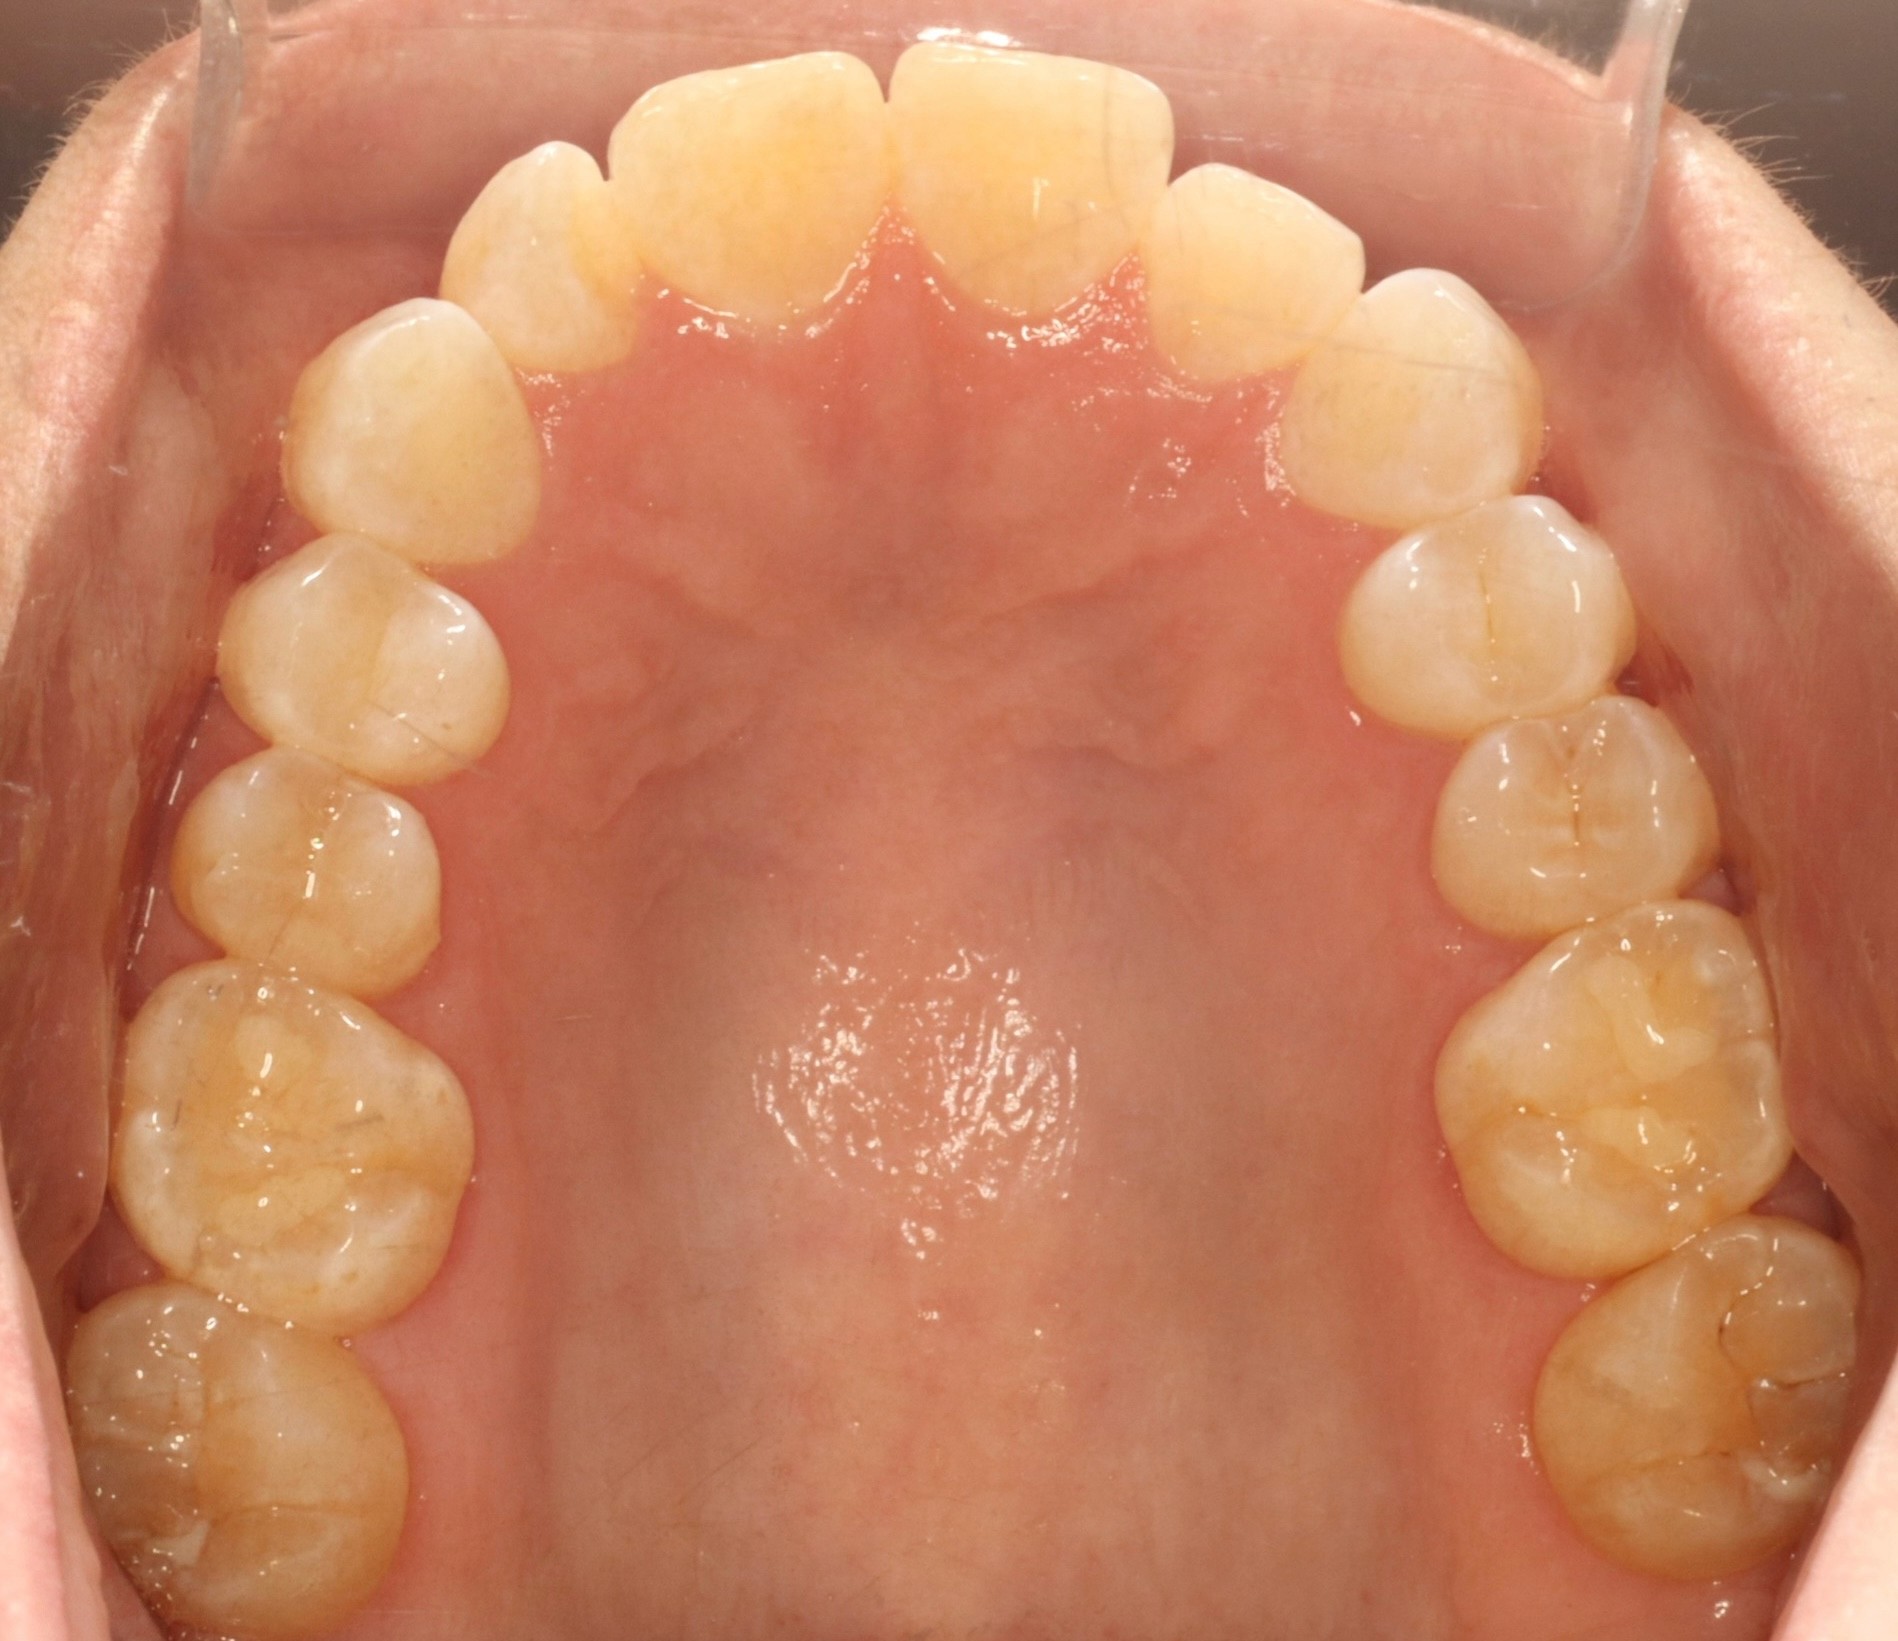

Initial treatment

INTRAORAL